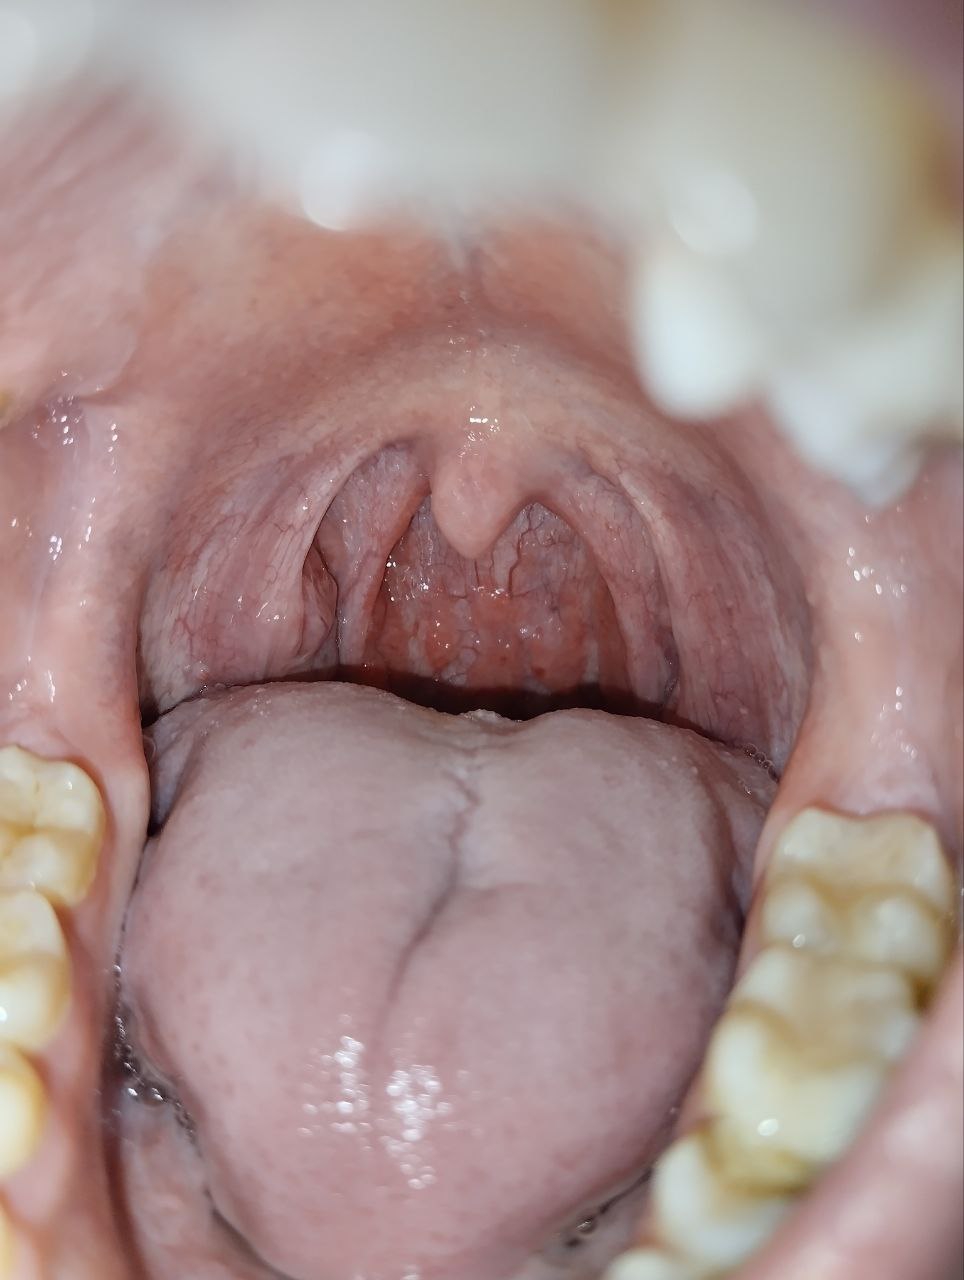

Фарингита -тред. Горло красное всегда, глаза побаливают, отëчность, под челюстью узлы немного непр

Фарингита -тред. По совместительству ЛОР-тред.

Горло красное всегда, глаза побаливают, отëчность, под челюстью узлы немного неприятно на ощупь, иногда хочется спать, усталость постоянная, вроде посев делал давно ничего не нашлось, температуры нет.

Ну отëк спал, но горло такое же красное.